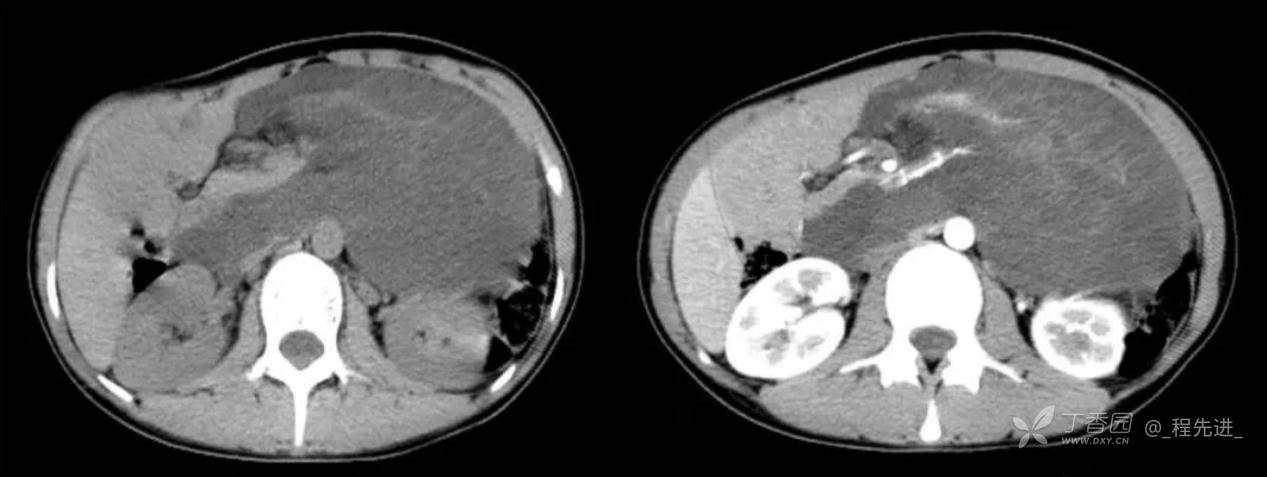

患者性别:女

患者年龄:24岁

主诉:腹痛、发热一天

现病史:一天前无明显诱因出现腹痛并发热不适,伴恶心、干呕,诊所肌注药物(具体用药不详),无缓解,无明显尿频、尿痛。

体格检查:腹肌稍紧张,右上腹部轻压痛,右肾区叩痛